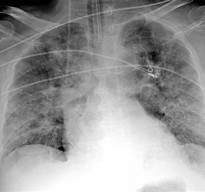

As an expert in all things medical, you are asked to correlate the images below (A-D) with the potential medical complications/causative agents (1-4)

A B

C D

1 2

3 4